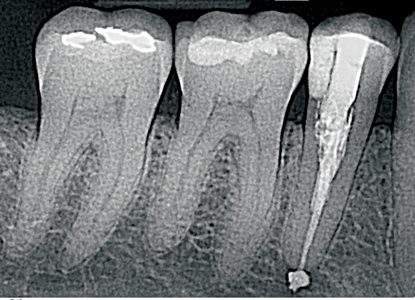

Successful Endodontic Treatment of Internal Cervical Root Resorption

Internal Cervical Resorption

Using Er,Cr:YSGG 2780nm and Diode 940nm Laser Systems: A Three-Year Follow-Up Case Report Abstract Endodontic therapy for teeth diagnosed with irreversible pulpitis has been in use for many years, and continues to be the standard of care in the dental practice. In simple cases, where mechanical instrumentation and chemical irrigation can achieve sufficient cleaning and … Read more